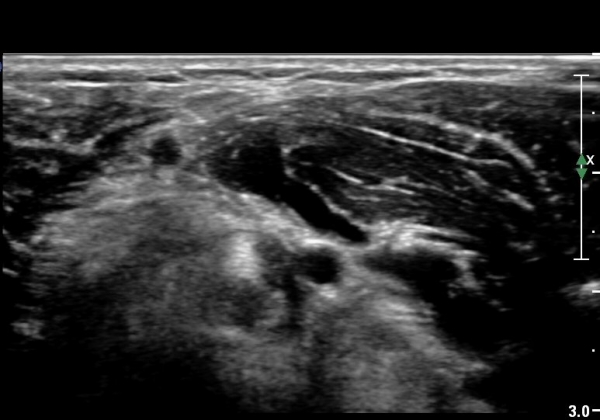

ŽÃËÀÚ¸¦ Á¶±Ý ¸»´ÜÀ¸·Î À̵¿Çϰí ŽÃËÀÚ¸¦ ¸Ó¸®ÂÊÀ¸·Î ±â¿ïÀÌ´Ï À̵ιڱٰÇÀÌ ¶Ñ·ÈÇÏ°Ô °üÂûµÇ´Âµ¥ À̵ιڱٰÇÀÇ ºÎÁ¾ÀÌ °üÂûµÊ(±×¸² 3).